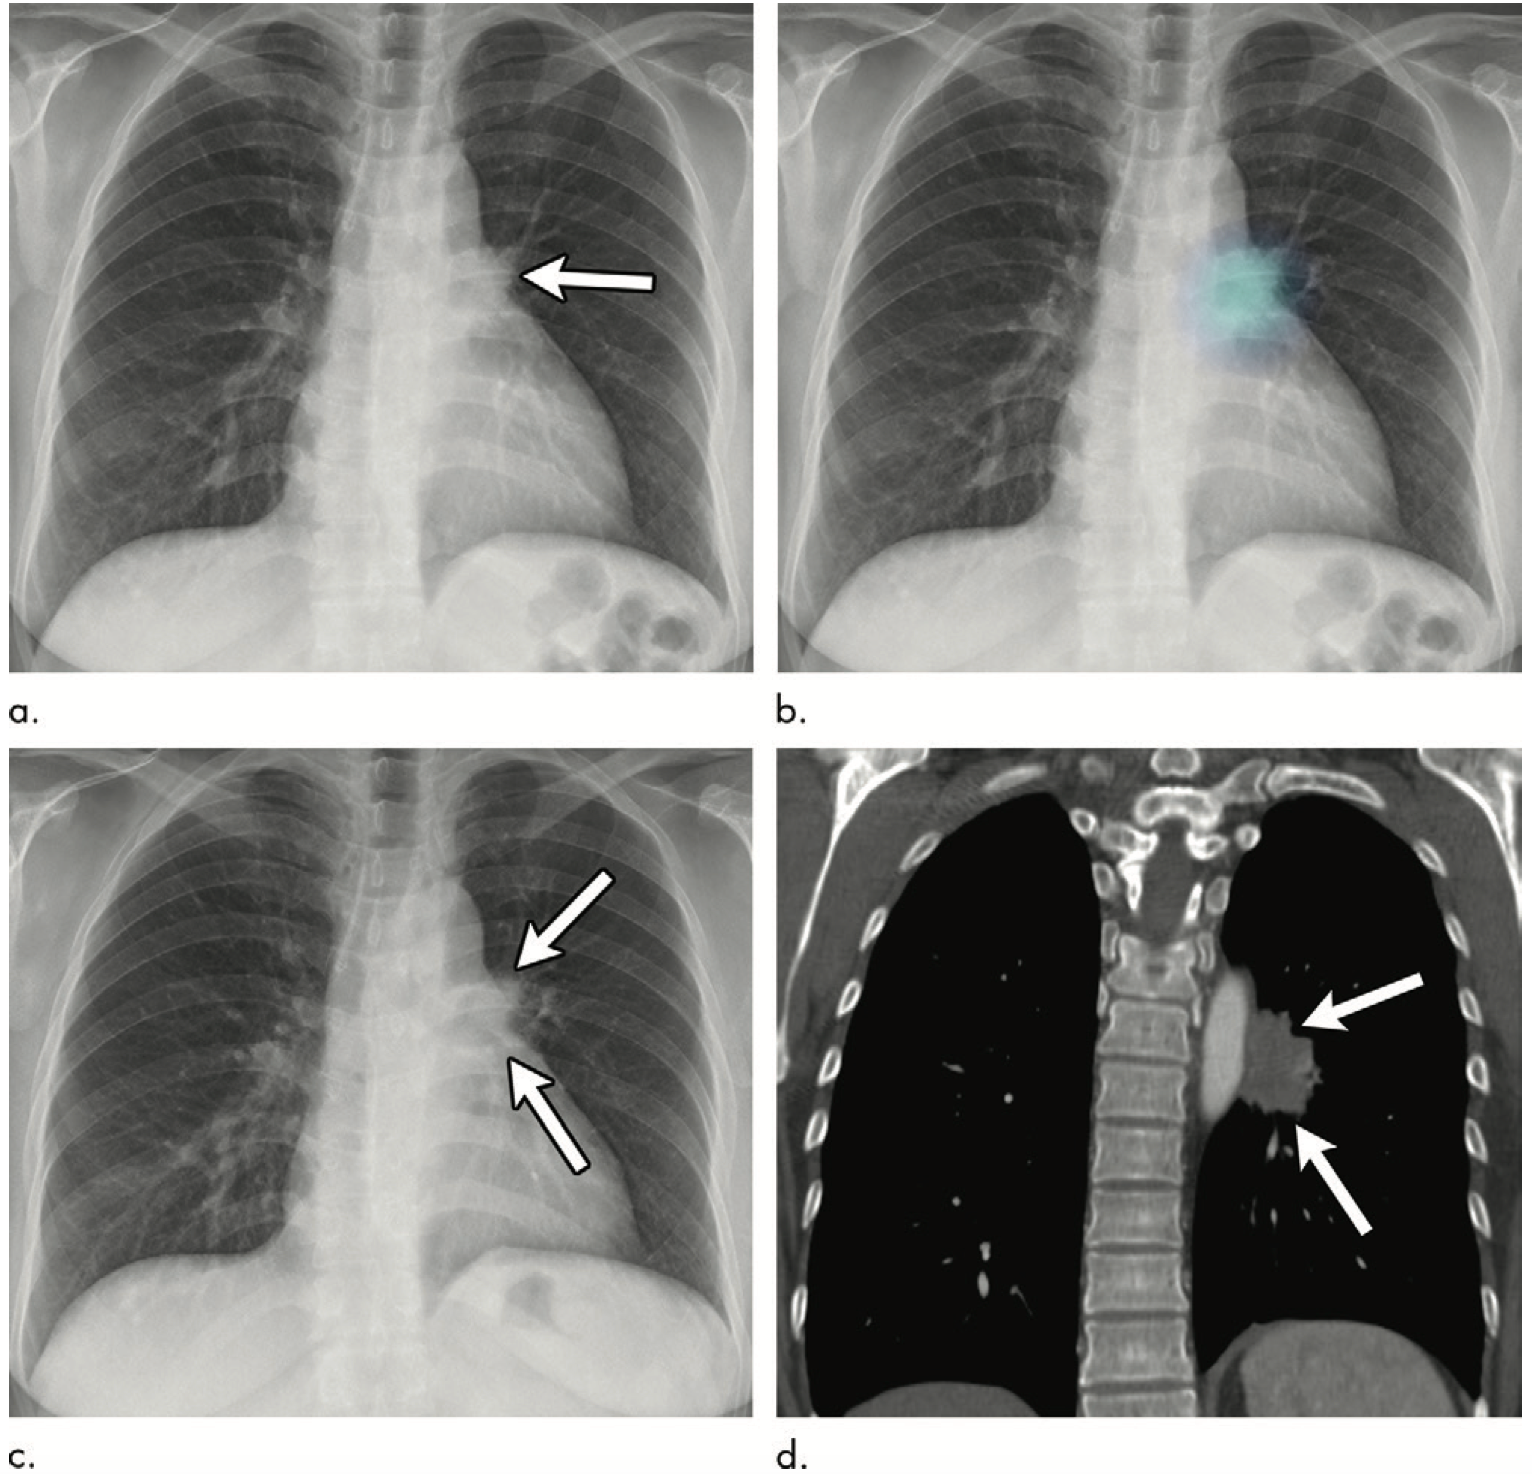

Chest X Rays 16 Subtle But Key Findings You Need To Know